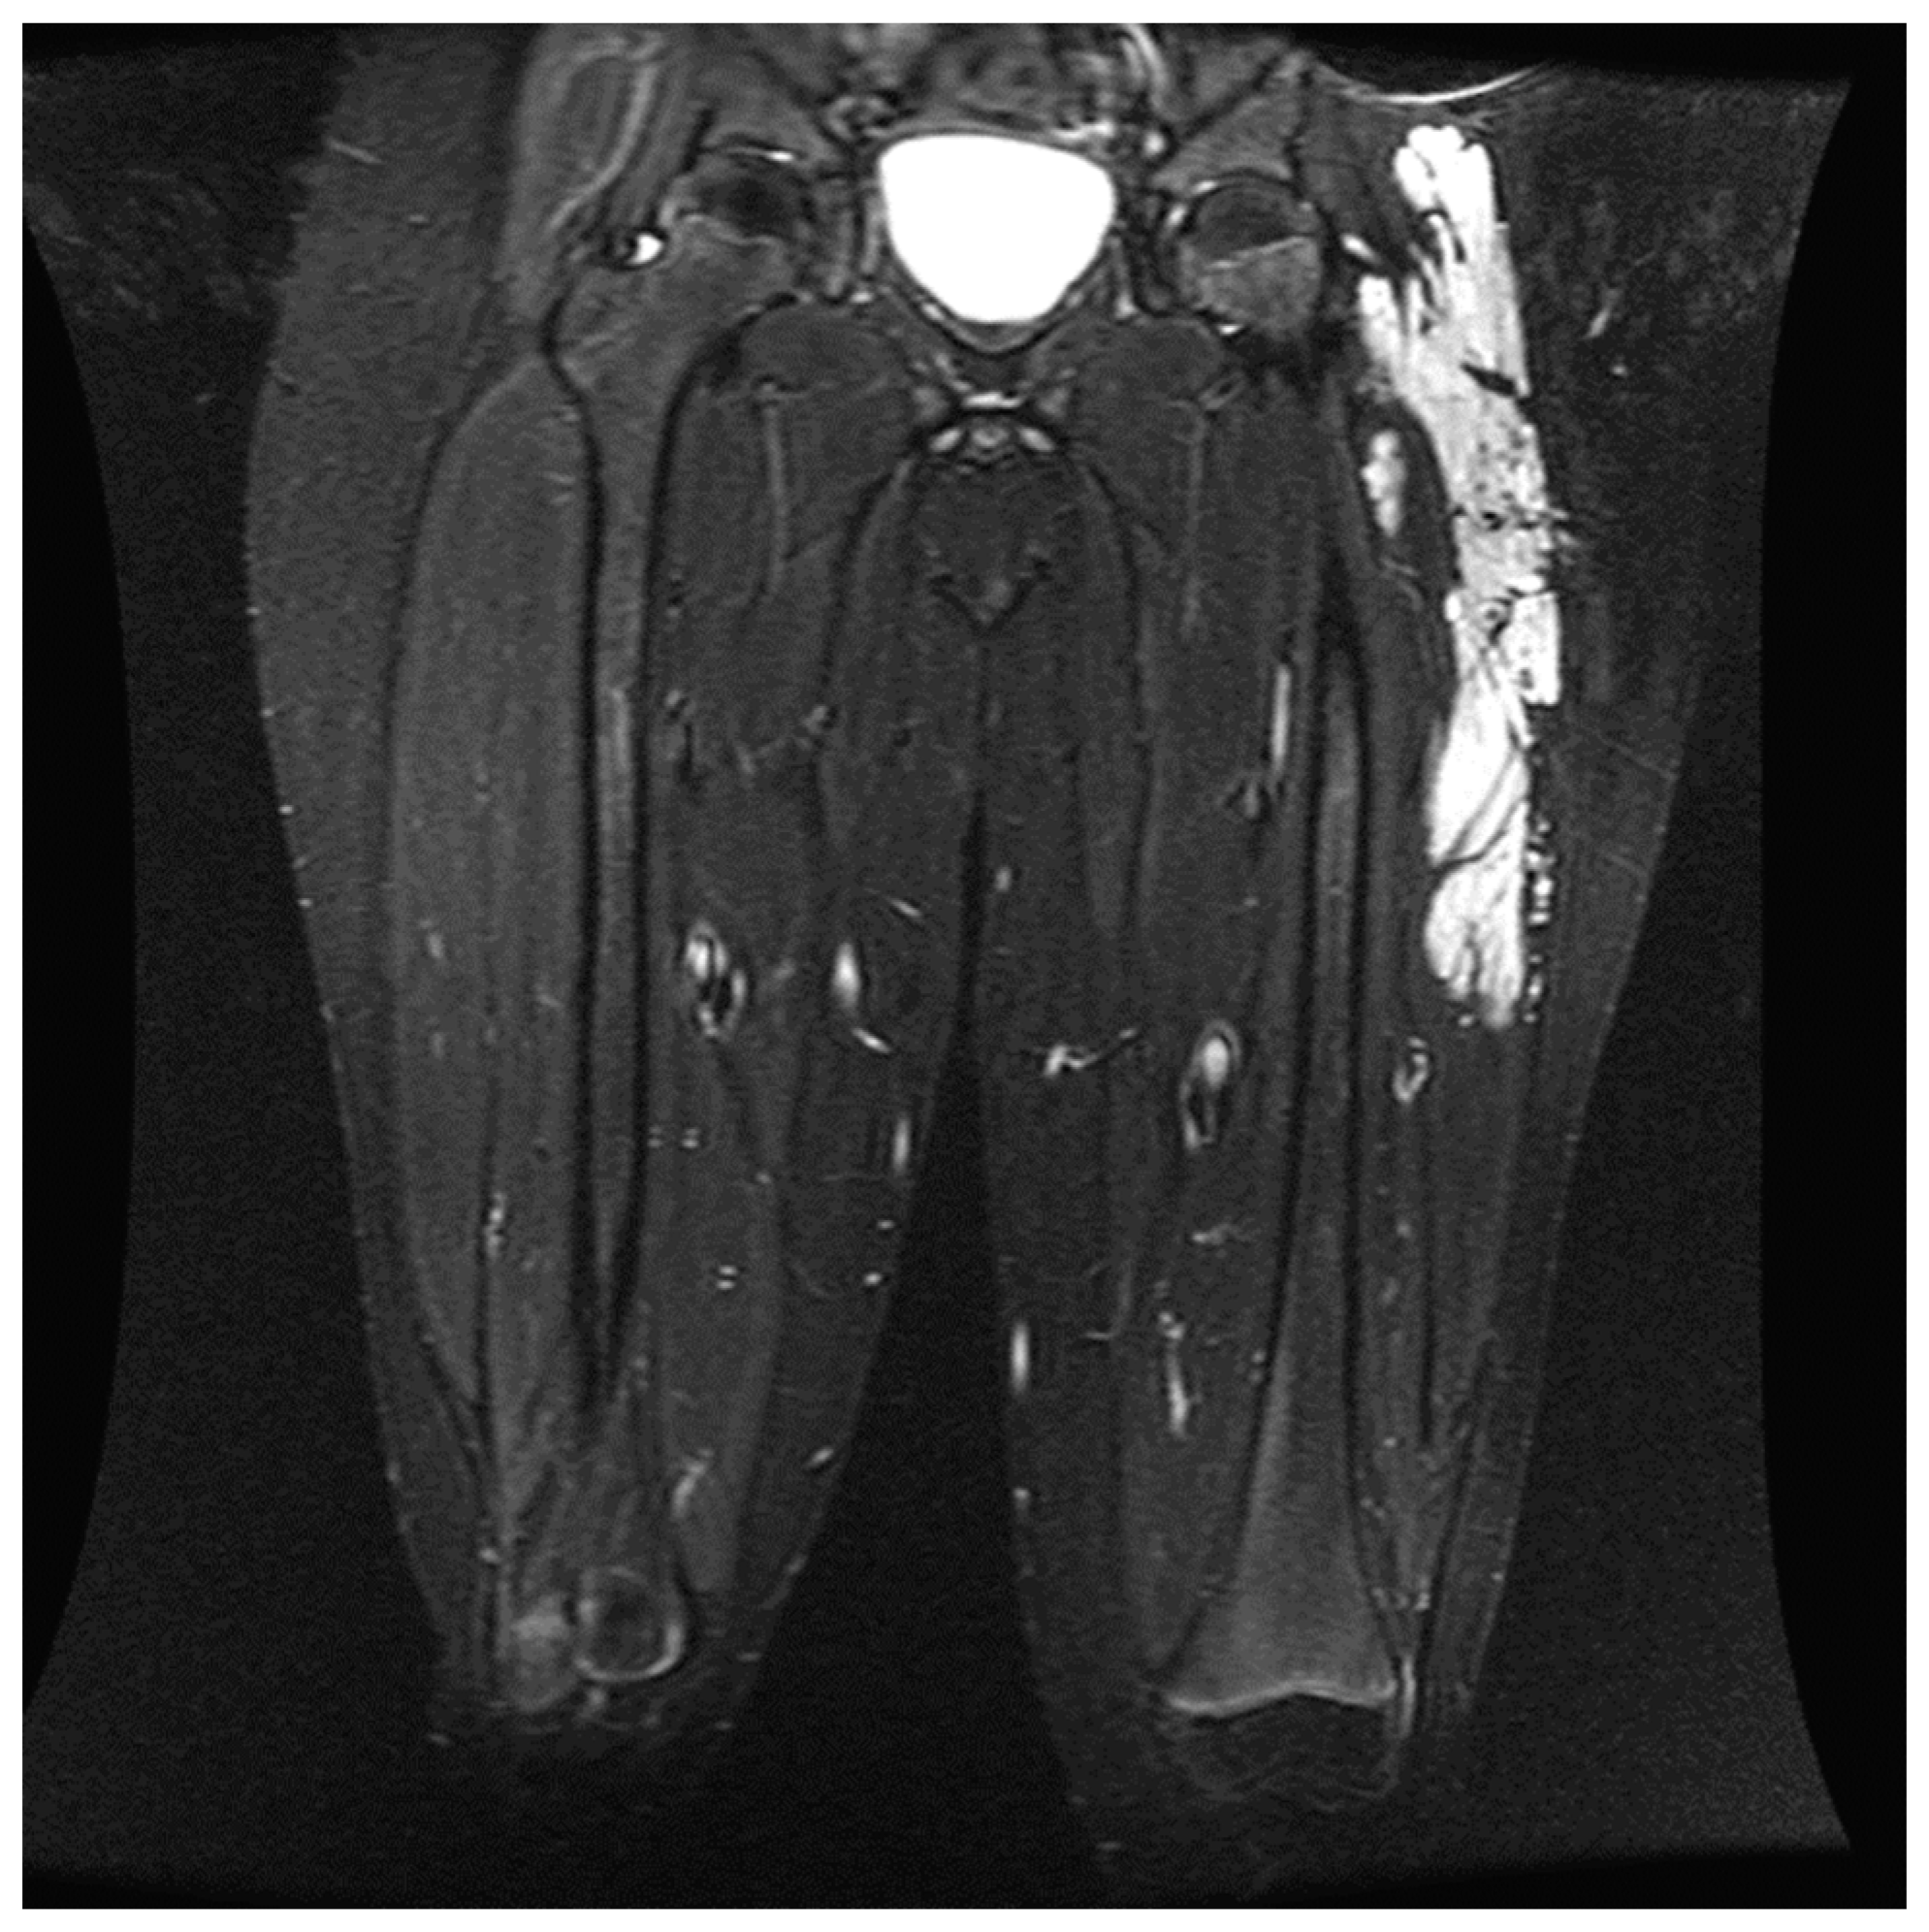

• When performing peripheral nerve blocks in pediatric patients undergoing embolization or vascular therapy, it is essential to consider the child’s location and size of the vascular malformation. Vascular malformations are frequently seen in children, with the most common area being in the head and neck [14]. Our retrospective study had similar results, with 39.6% of the vascular malformations treated in the study in the head and neck region. Most head and neck malformations are not amenable to a peripheral nerve block due to the location of the sensory nerves in the face and neck. The upper and lower extremities were the second and third most common sites for therapy, aligning with the most common areas of malformations. These locations are much more amenable to peripheral nerve blocks as nerve blocks have proven safe and effective in treating pain in the extremities. Careful consideration must be given when determining if a patient should receive a peripheral nerve block for therapy (Figure 3). In this study, the proceduralist requested a peripheral nerve block for patients based on the location of the malformation and the likelihood of the treatment causing severe pain. Some of the nerve blocks performed were for patients who had previously received therapy without nerve blocks but developed severe pain in the postoperative setting (Figure 4).

Figure 3. Coronal T2-weighted fat-suppressed image shows an extensive hyperintense slow flow vascular malformation consistent with a venous malformation involving the intramuscular and subcutaneous planes of the left lateral thigh and hip. During the specified range of dates, the child received four procedures. Each procedure was performed with a lumbar plexus nerve block for postoperative pain control.